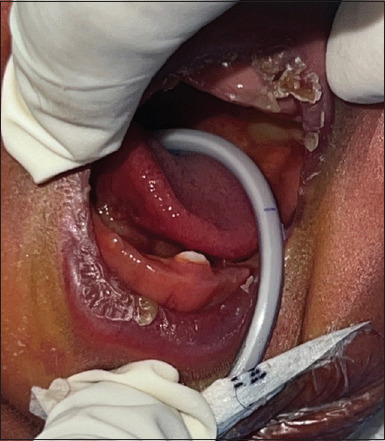

贝克维斯-魏德曼综合征(BWS)是一种罕见的遗传疾病,其特征是躯体过度生长,易患各种疾病,包括肿瘤。这个病例报告了一个25天大的BWS男婴,表现为巨舌、肝脾肿大、高胰岛素性低血糖、牙龈肥大和上颌弓囊性病变,促使儿科医生、儿科医生、口腔外科医生和口腔病理学家进行多学科合作。患者还出现了Hebling's III类出生牙。按照所有的注意事项,在局部麻醉下拔牙。该病例报告的突出之处是首次记录了确诊的BWS病例中出现的先天性牙齿,有助于了解罕见遗传综合征的口腔表现,并强调了在管理这一复杂遗传综合征时及时干预和综合医疗的必要性。

Beckwith-Wiedemann syndrome (BWS) is a rare genetic disorder characterized by somatic overgrowth and an increased predisposition to various medical conditions, including neoplasms. This case report presents a 25-day-old male infant with BWS exhibiting macroglossia, hepatosplenomegaly, hyperinsulinemic hypoglycemia, gum hypertrophy, and cystic lesions in the maxillary arch, prompting a multidisciplinary collaboration of a pediatrician, pedodontist, oral surgeon, and an oral pathologist. The patient also presented with Hebling's Class III natal tooth. Following all the precautions, the natal tooth was extracted under local anesthesia. This case report stands out for documenting the presence of a natal tooth in a diagnosed case of BWS for the first time, contributing to the understanding of oral manifestations in rare genetic syndromes and underscoring the need for timely intervention and comprehensive medical care in managing this complex genetic syndrome.